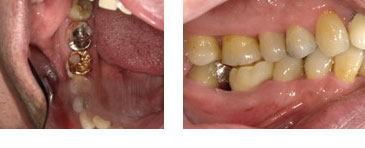

左上6番 サイナスリフト(上顎洞底挙上)によるインプラント埋入

BEFORE

AFTER

| 金額 | ¥485,000(税抜) |

| 期間 | 約3ヶ月 |

| リスク | オペから6週までは過大な力がかかると骨の2次安定が得られないことがあるため、注意を要する。 |